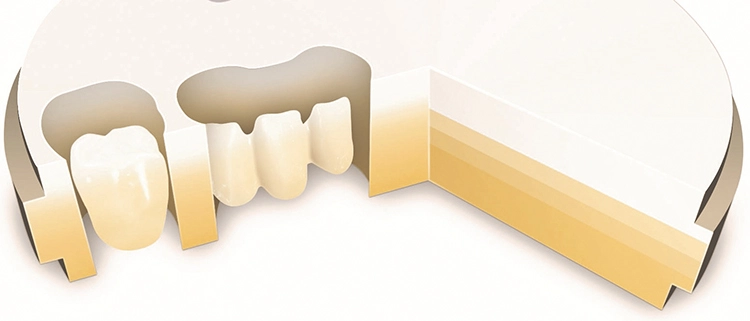

Das Frakturrisiko bei Kronen hat sich deutlich gemindert durch den Einsatz von festigkeitsgesteigerten Keramikwerkstoffen – z.B. mit Lithiumdisilikat, zirkonoxid-dotiertem Lithiumsilikat und Zirkonoxid im monolithischen Kronendesign (Abb. 2). Die Überlebenswahrscheinlichkeit liegt auf jenem Wert, der auch Gussrestaurationen zugeschrieben wird. Kuraray

Der Quantensprung begann damit, dass durch den Umbau der keramischen Matrix die hohe Festigkeit mit der Ästhetik verbunden wurde. Dafür wurden differenzierte ZrO2-Solitäre mit den lichtoptischen Merkmalen von Dentin und Schmelz akkumuliert mit der Folge, dass unterschiedliche Eigenschaften für Festigkeit, Farbe, Lichttransmission und Transluzenz schichtweise in einem Fräsblock zusammengeführt wurden. Dieses monolithische Zirkonoxid weist sich je nach Anbieter in unterschiedlichen Kombinationen als 3Y/4Y/5Y-TZP aus.